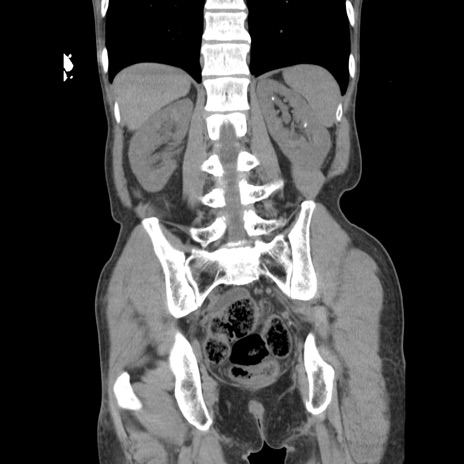

症例11(冠状断像)

【症例】 60歳代男性

【主訴】 下腹部痛

【現病歴】 本日夜中より下腹部痛の症状認め、受診。

【既往歴】 膀胱癌(膀胱全摘+尿管皮膚瘻術) 、胃癌術後

【身体所見】 BT 35.3℃、PR 58/min、BP 136/98mHg、腹部平坦、軟、腸蠕動音±、ストマ留置あり、左上腹部~正中部に圧痛あり、反跳痛なし。

【データ】WBC 5100、CRP0.01

横断像